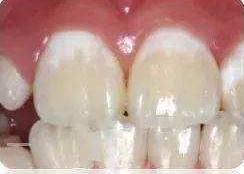

*个别牙齿上出现的白斑(如门牙):牙釉质发育不全(轻度),常出现在切牙中部和切端。

牙齿局部脱矿(下图)